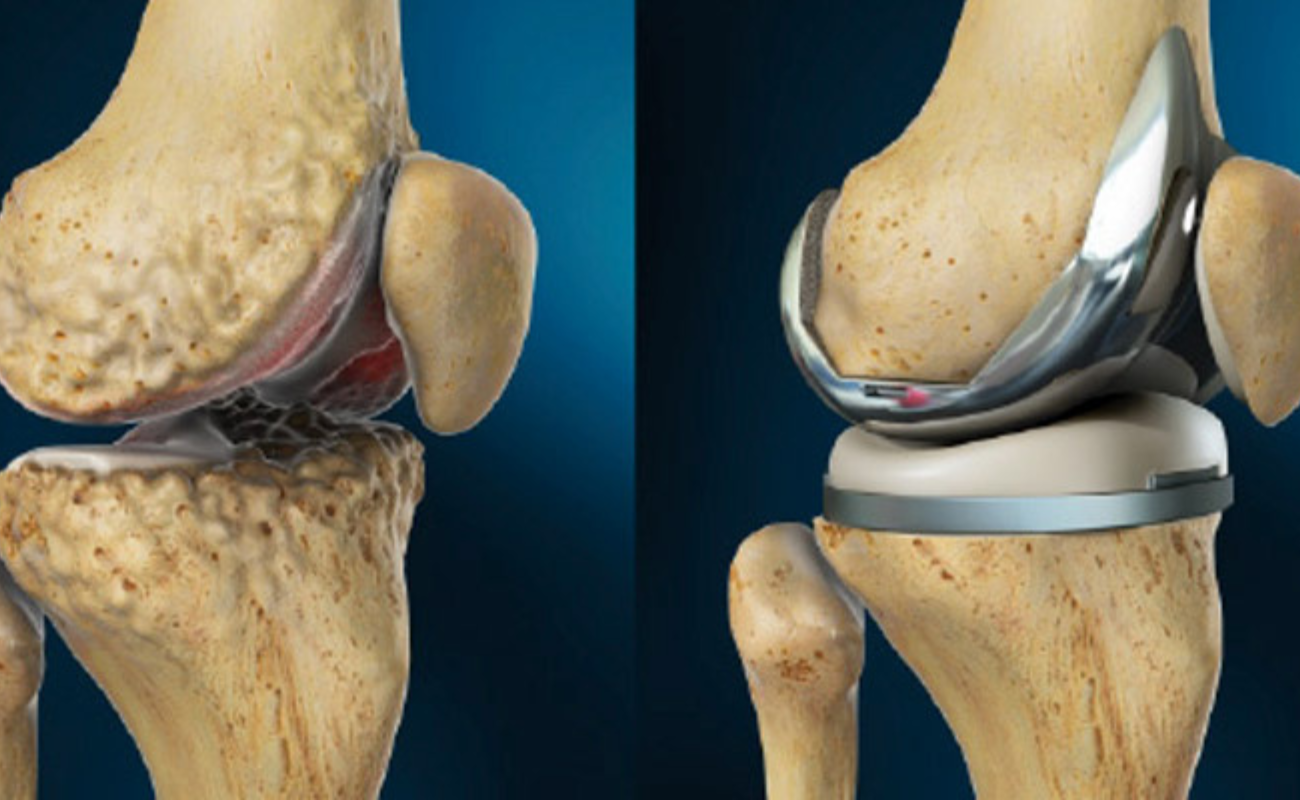

Osteoarthritis

Osteoarthritis leads to loss of cartilage when rate of cartilage damage exceeds the rate of repair. Cartilage is necessary to prevent bones from rubbing against each other. When the cartilage cover is lost, the bones come into contact and result in painful movement.

Knee Replacement Surgery: When Is It Time?

Knee pain and mobility issues can significantly impact a person's quality of life. When conservative treatments fail to provide relief and daily activities become increasingly challenging, knee replacement surgery may be considered.

Preparing for Knee Replacement Surgery: A Comprehensive Guide

Facing knee replacement surgery can be a challenging yet hopeful journey towards renewed mobility and reduced pain. To embark on this path confidently,

Knee Replacement Surgery: A Comparison of Traditional and Robotic Techniques

When it comes to addressing debilitating knee pain and restoring mobility, knee replacement surgery has been a transformative solution for many individuals.